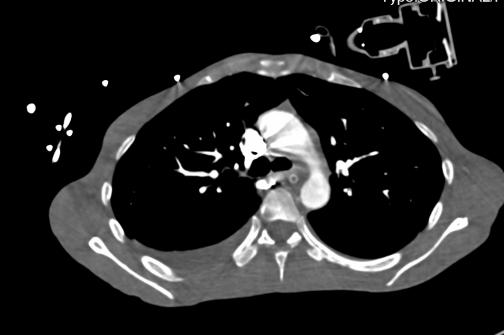

2021-4-29 CTPA:肺动脉干、左右肺动脉及其分支未见狭窄及明显充盈缺损。右肺、左肺下叶见斑片影、磨玻璃影及实变影。

患者青年女性,慢性病程;主要表现为腹胀、呼吸困难,术后出现意识障碍、II型呼吸衰竭。经呼吸机辅助呼吸、对症支持等治疗后,患者意识恢复但呼吸困难无明显改善;既往有有粉尘接触史。查体见患者极度消瘦、营养不良,双肺呼吸音粗,可闻及散在湿啰音。血气示II型呼吸衰竭、高碳酸血症,轻度贫血,低蛋白血症,电解质紊乱,炎症指标、肌酶、BNP升高,院外腹水检查示漏出液,未见肿瘤细胞;胸部CT:双肺斑片影,抗感染治疗后病灶吸收;腹部增强CT:双侧附件区分别混杂密度团块影,内见多发囊泡影;心脏彩超:右心稍大,重度肺动脉高压。